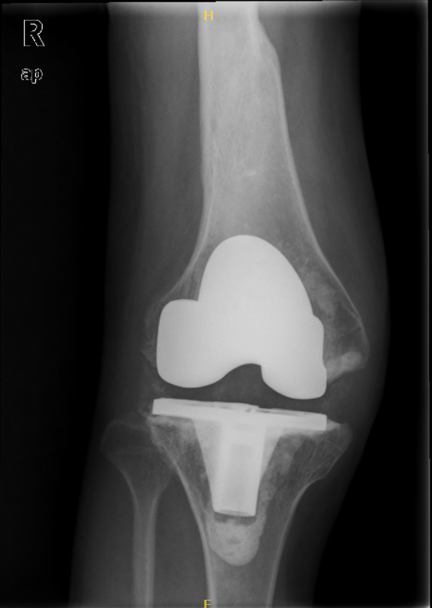

1、术后影像

3、假体选择:患者关节畸形明显,具有骨质疏松,但考虑患者年龄,首选后稳定性膝关节假体(术中备限制性假体)。